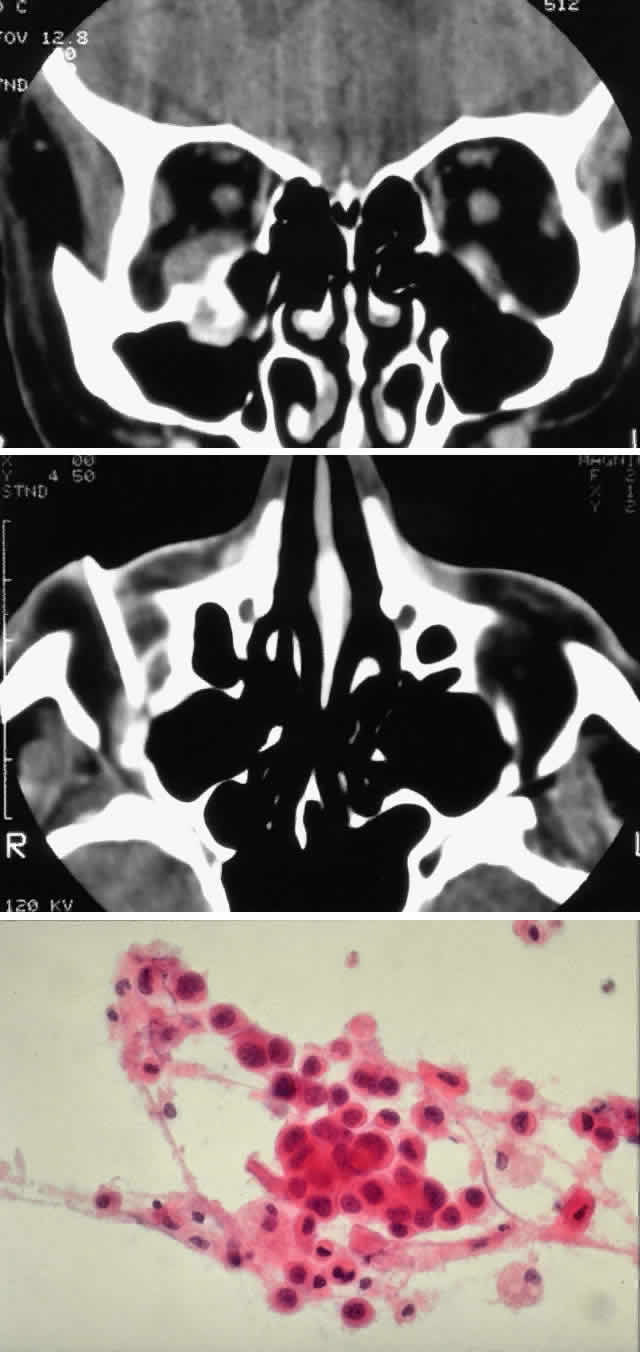

Radiologic findings consist of either focal or widespread destruction of the sinuses, with invasion of the adjacent structures by a solid tumor mass (Fig. 2). The mass is usually large; however, sometimes it may be relatively small but may extend to adjacent structures, particularly in the case of adenoid cystic carcinoma (Fig. 3). The sinus and orbit may be the only structures involved, but there is frequently extension to the base of the skull.

Fig. 2. A 32-year-old woman presented with a 1-month history of sinus congestion and nasal obstruction unresponsive to antibiotics. In the 1 week preceding the initial exam, the right eye became progressively more prominent and showed tearing and redness. On examination, there was mild edema of the lower lid and dysesthesia in the distribution of cranial nerve V2, and the globe was displaced 6 mm laterally and 5 mm anteriorly. There was mild limitation of abduction, chemosis, and nasal choroidal folds. An axial CT scan revealed a diffuse, destructive soft tissue mass centered in the superior nasal passage and ethmoid sinuses extending into the right orbit in contiguity with the medial rectus (A). On enhanced coronal view, the tumor was noted to involve the right maxillary antrum and to extend superiorly into the anterior cranial fossa (B). Biopsy of the sinus (C) revealed an alveolar-type rhabdomyosarcoma (muscle stain, × 320).

Fig. 3. A 73-year-old man presented with a 2-year history of infraorbital numbness and burning sensation, which had progressed to include the supraorbital region, forehead, and lower face during the past 6 months. He had been treated with radiotherapy for prostate carcinoma 7 months before orbital presentation. Examination was significant for proptosis of 2 mm and dysesthesia, including corneal numbness, in all three divisions of cranial nerve V. CT scan revealed a soft tissue mass in the inferior orbit contiguous with the inferior rectus muscle (A). The lesion extended through the infraorbital canal to involve the pterygopalatine fossa and was associated with soft tissue hanging into the upper portion of the maxillary sinus. An axial CT scan-guided aspiration biopsy was performed (B) and revealed squamous cell carcinoma. Groups of cohesive malignant squamous epithelial cells (C) were noted to have pleomorphic nuclei and abundant eosinophilic to orange cytoplasm, with no features of mucinous differentiation (H & E, × 320). (C from White VA, Rootman J: Orbital pathology. In Albert DM, Jakobiec FA (eds): Principles and Practice of Ophthalmology, Vol 4, p 2342. Philadelphia, WB Saunders, 1994.)